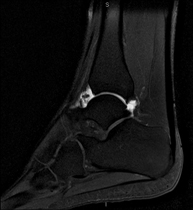

Exploración para el estudio de la articulación y sus frecuentes lesiones de ligamentos (esguinces) así como de la afectación de otras estructuras como el cartílago o el hueso. También es de gran utilidad para diagnosticar alteraciones en el tendón de Aquiles (tendinitis, roturas). Duración de aproximadamente 20 minutos. No emplea radiación ionizante. - RM Pie